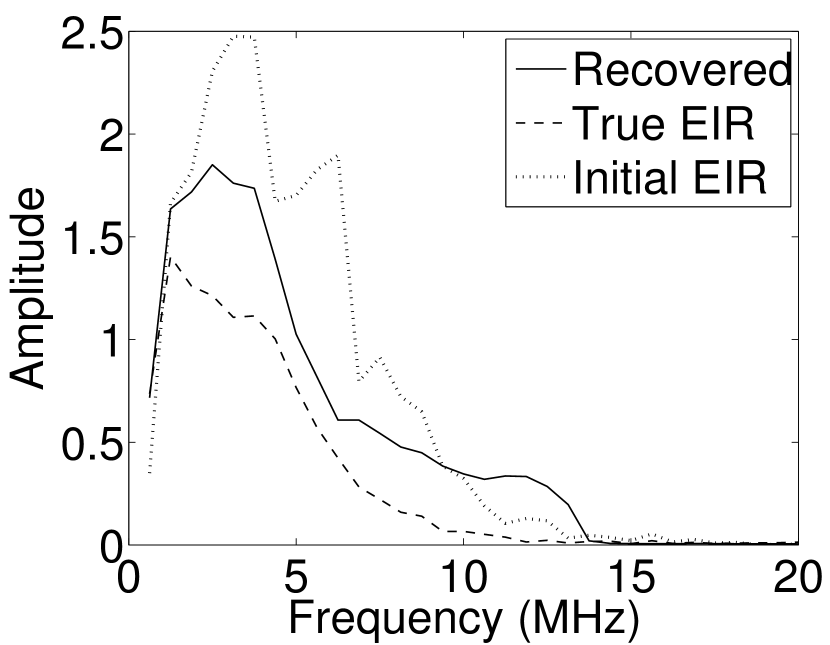

As shown in Figure 6, when the error in the EIR was small (e.g., as with the EIR in Figure 6(a)), images were reconstructed with high accuracy using the VP algorithm. When the perturbations in the EIR were stronger (e.g, as in Figure 6(c)), artifacts and distortions in the reconstructed images were still significantly reduced by use of the VP algorithm; however, larger values of the regularization parameters had to be applied. When as in the initial EIR in Figure 6(e), no improvement was observed in the image reconstructed by use of the VP algorithm.

Images reconstructed by use of the VP algorithm with different values of the regularization parameter values are shown in Figure 8. The recovered EIRs and their corresponding Fourier spectra are shown in Figures 9 and 10, respectively. The RMSE values are computed and displayed together with the corresponding images. As expected, the images reconstructed with smaller values of contain higher noise levels, while images using larger possess a reduced noise level. However, larger values of also caused artifacts in the reconstructed images. The same observation can be made for the effect of the regularization parameter on the recovered EIR. One also observes that the reconstructed images and EIRs depend continuously on the regularization parameters and , i.e. small changes in the regularization parameters cause minor changes in the reconstructed images and EIRs.